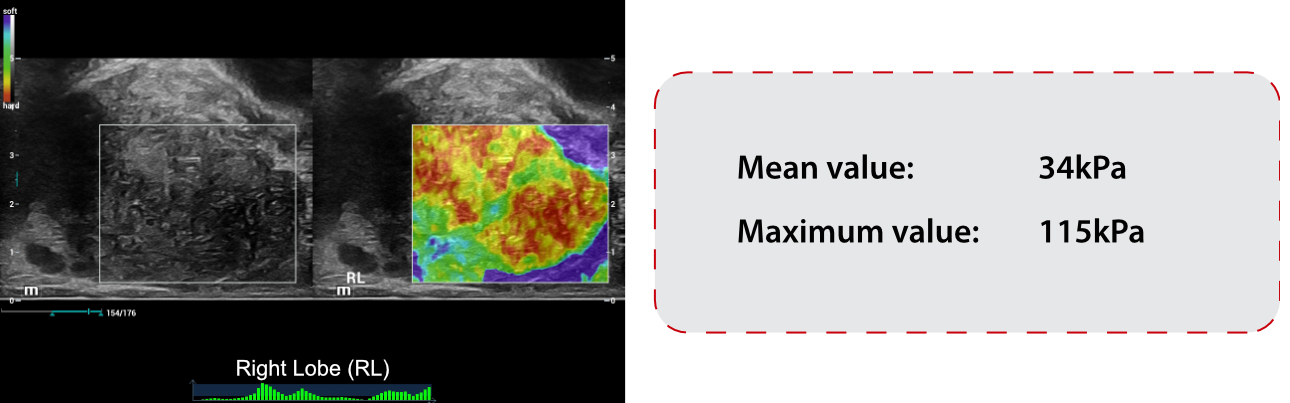

Elastography Findings:

SWE ŌĆō Shear Wave Elastography:

- SWE showed abnormal stiffness measurements of RL, which mean stiffness value was 34kPa and max stiffness value was 115kPa.